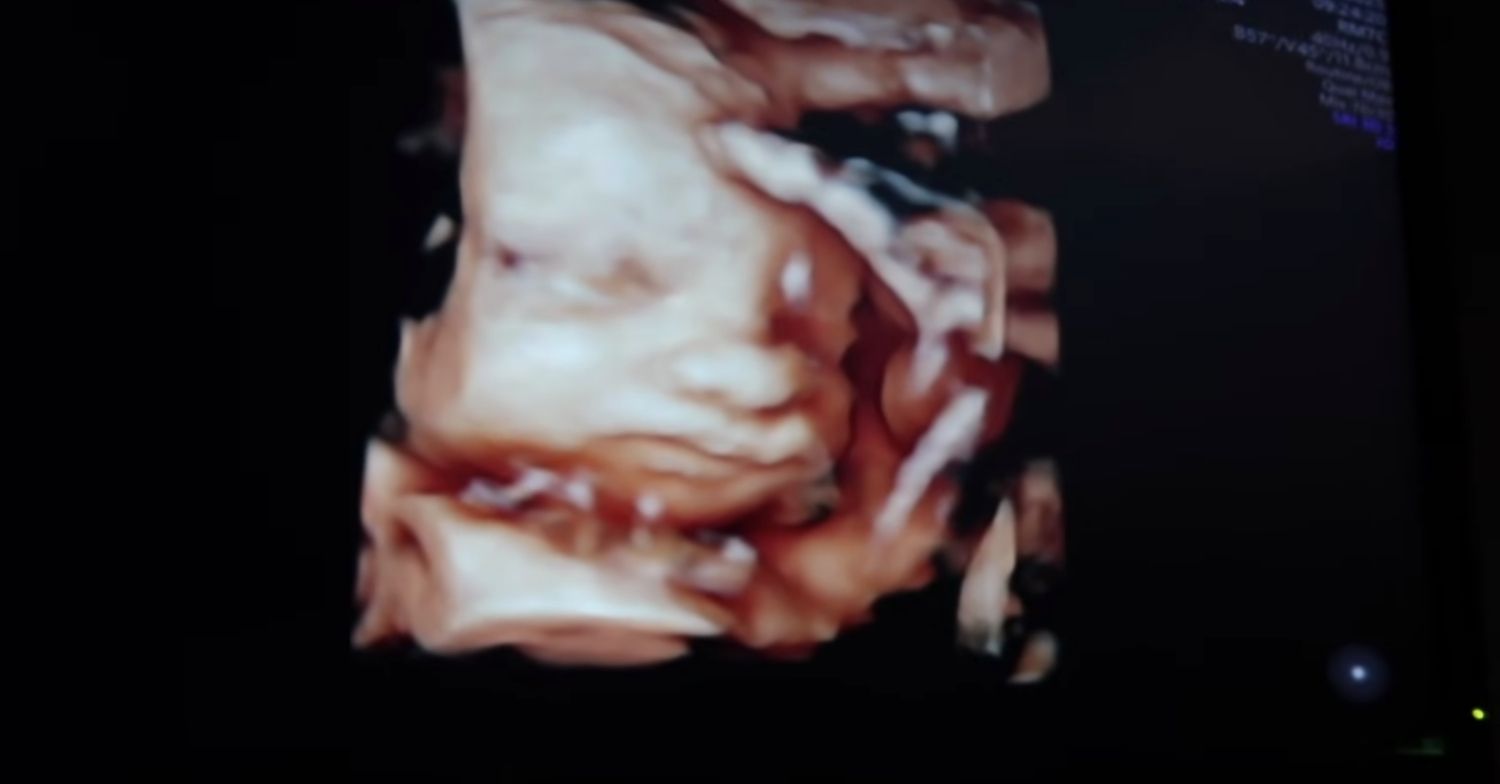

Pregnant Dianne Buswell and Joe Sugg have delighted fans after sharing a 4D scan of their baby.

And this week, Dianne and Joe – who started dating in 2018 – headed for a 4D scan of their bundle of joy.

In a recent YouTube video on Joe’s account, Joe brought viewers along to his and Dianne’s 4D scan of their unborn baby.

“So all those whooshing noises are him moving,” said the midwife, as she scanned Dianne’s stomach with the technology. Strictly star Dianne said: “I can feel him!” as Joe quipped: “Baby keep still!”

Joe then filmed his unborn baby’s face as he popped up on the screen. An emotional Joe proclaimed: “Aww, so cute!” Dianne said: “His little face! Oh my gosh, he’s so cute.”

Joe added: “The cutest little nose,” before he turned the camera around to show him overcome with emotion, as tears welled up in his eyes.

A stunned Joe mused: “It’s amazing that your body has made, like created bones inside it.” After the scan, Joe and Dianne headed to the waiting room. Looking at the photo of their unborn baby Dianne said: “Isn’t he so cute?!”

Joe then updated fans and said: “So his foot is basically up next to his head which I’m sure is fine.”

Joe then told Dianne: “I can safely say he’s got your nose.” Dianne agreed: “He’s definitely got my nose!”